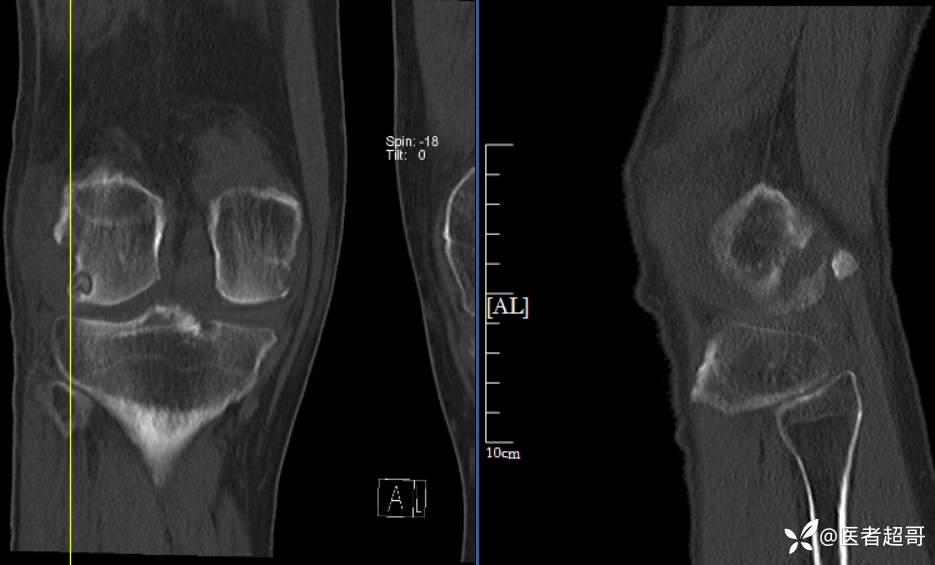

华夏览雄 等 2 位达人已点赞男性,55岁,右膝关节疼痛伴活动困难2年余

两年前外院行右膝包块切除术,术后病理为“肉芽肿”,具体不详,患者术后经常右膝关节积液,右膝活动困难,右膝疼痛明显

实验室检查:白细胞计数:9.0×10^9/L;葡萄糖(空腹):6.93mmol/L↑